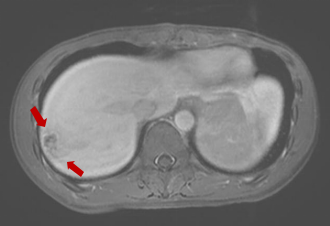

随后,入院查血常规提示嗜酸性粒细胞百分比大于40%,转氨酶明显升高,CT检查提示肝右叶占位性病变。上腹部磁共振增强提示肝右叶包膜下多发液性信号。肥大反应提示丙型副伤寒1:320,考虑沙门菌感染,这是一种由沙门氏菌属细菌引起的常见食源性疾病,可以通过受污染的食物或水传播。

磁共振显示:肝右叶包膜下见多处团片状、楔形病灶。